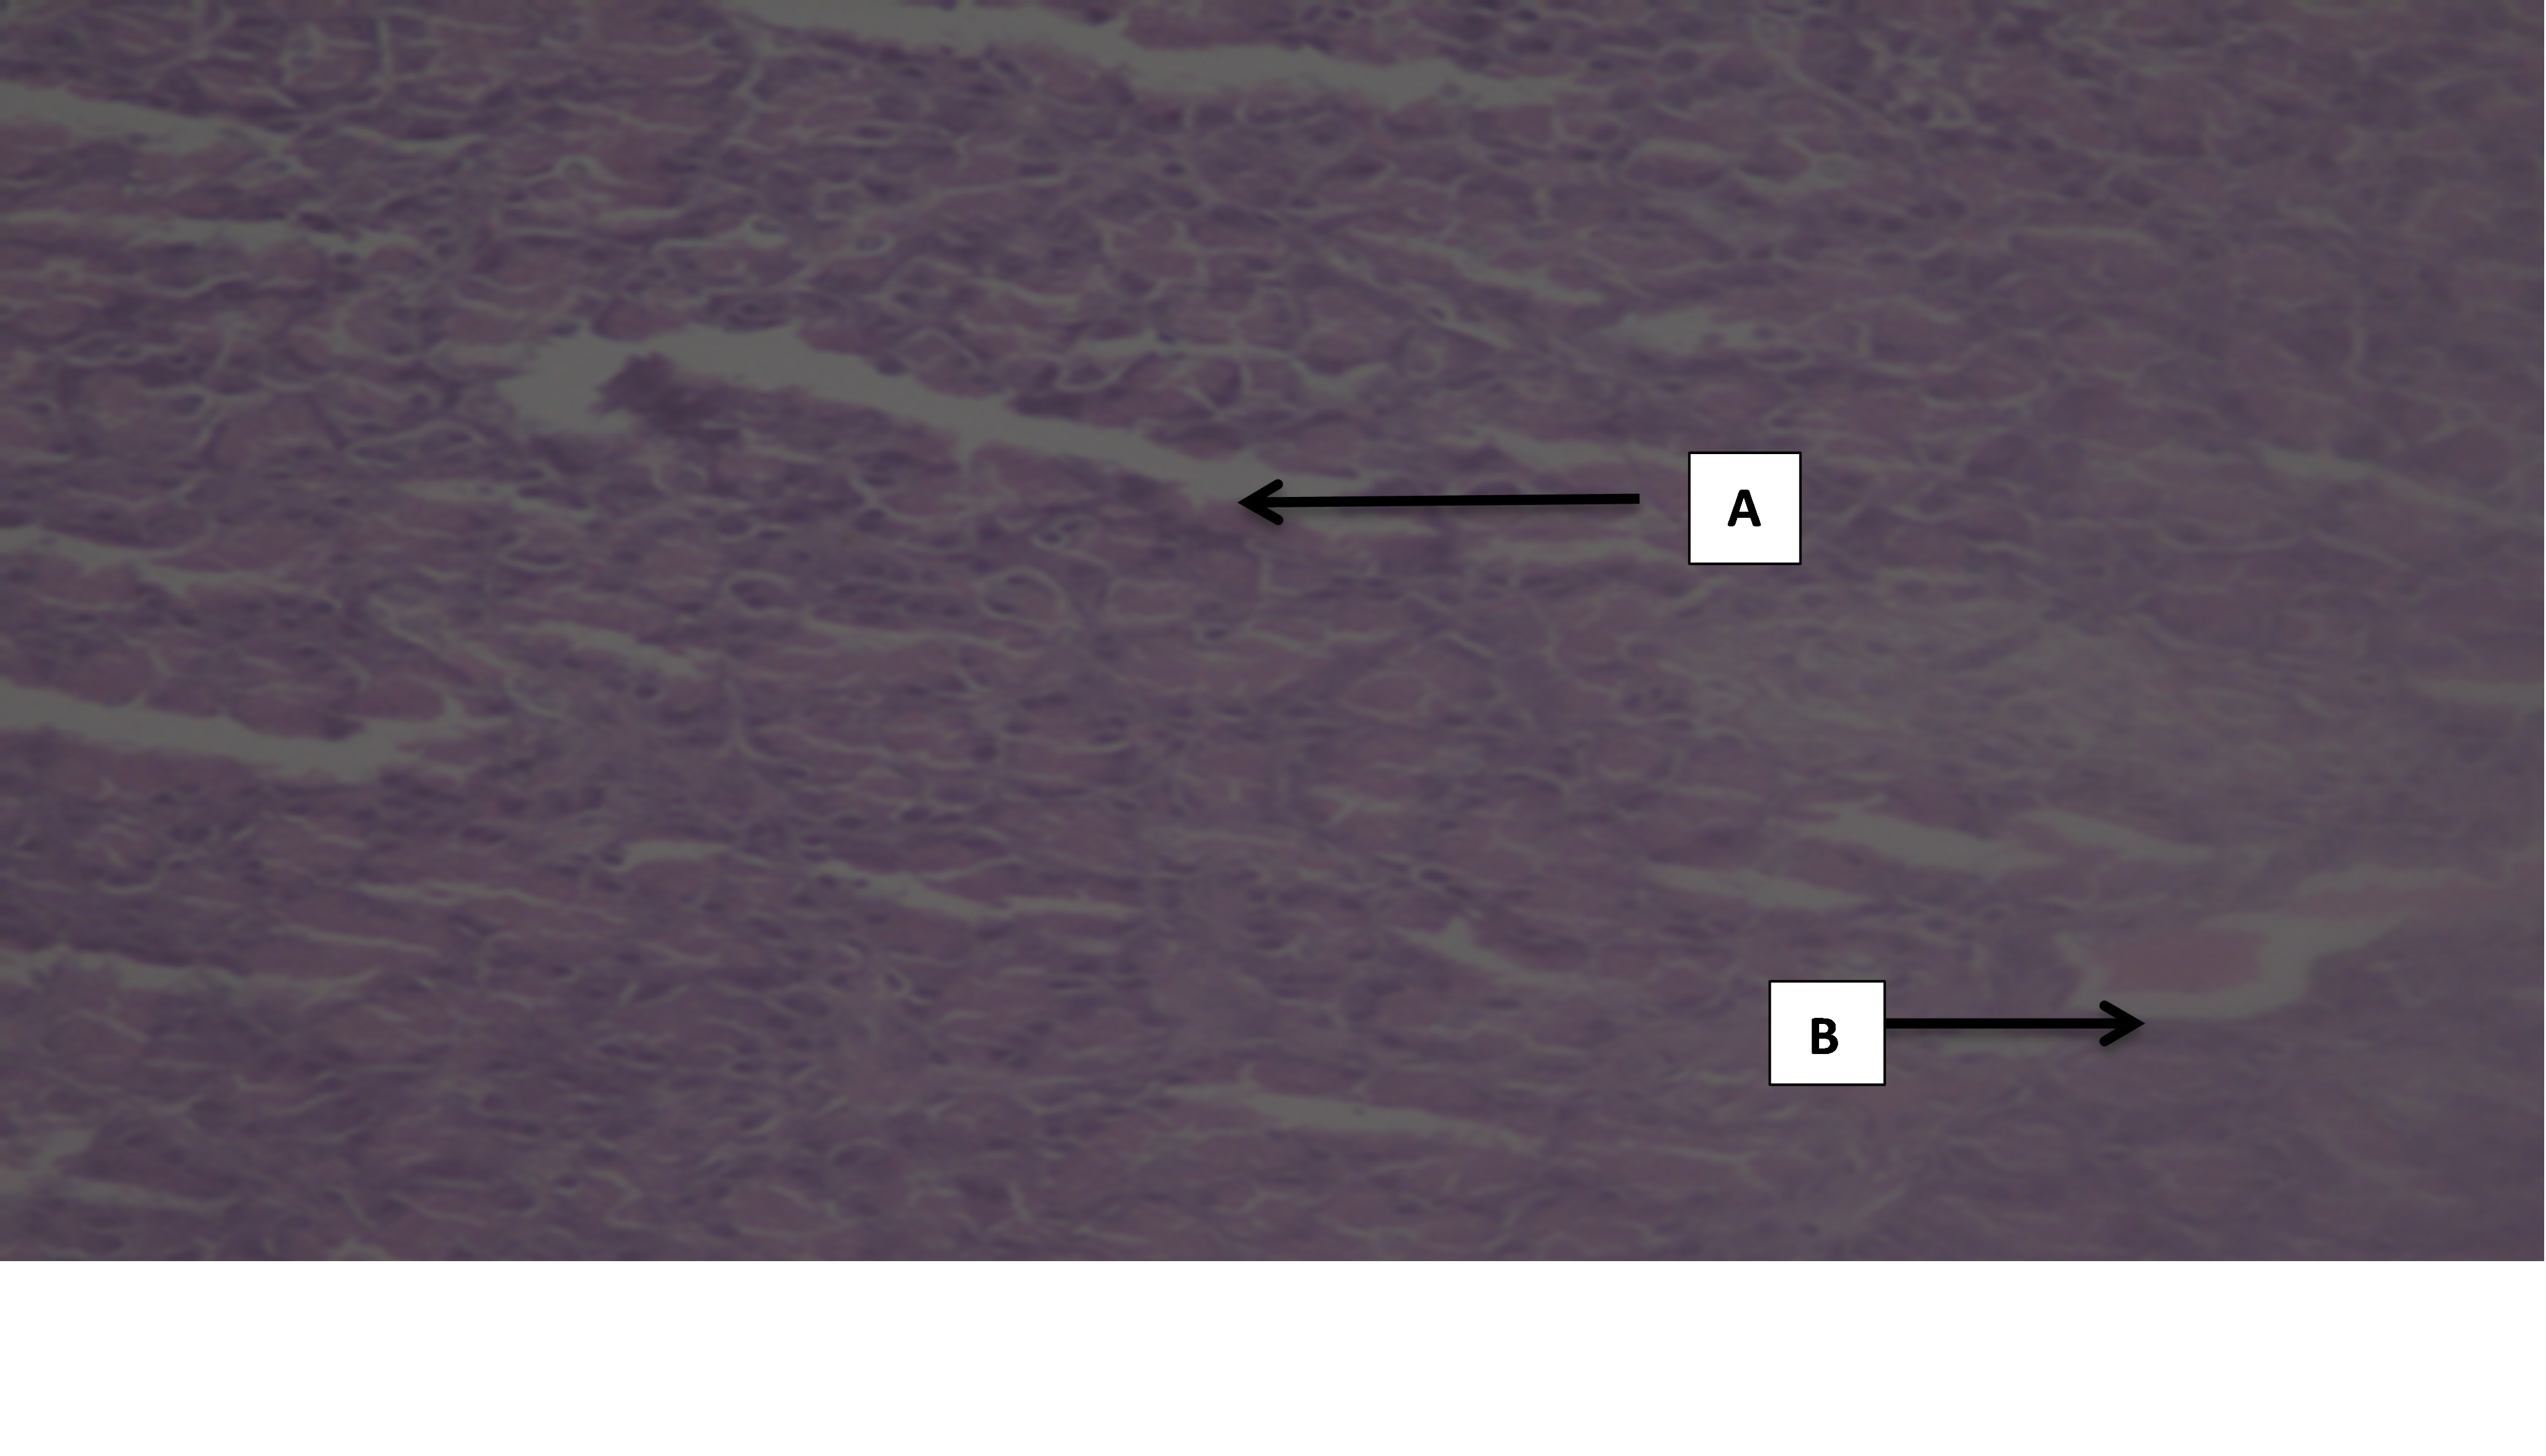

The photomicrographs of normal control group rats showed normal acini, and normal cellular population in the islets of Langerhans in pancreas as shown in (slide 1). Massive cell damage, extensive destruction of cell lining, inflammatory cells, and β-cell damage were seen in diabetic control group (slide 2). There was enlargement of β-cells, increase in vascular spaces with hyperplasia in standard group, i. e. Glibenclamide (slide 3).

The histopathological results of pancreas with FDLEE 100 mg/kg showed exocrine and endocrine tissue at most places intact with few areas showing presence of fatty tissue. The slight damage to the cell lining, slight damage to vasculature and haemorrhages with necrosis were also seen.

The microscopic changes showed significant improvement in the development of islet of Langerhans (slide 4). The microscopic changes in pancreas with FDLEE 200 mg/kg showed haemorrhage with necrosis, damage to the vasculature, normal cell population, slight β-cell enlargement.(slide 5) In the test group FDLEE 400 mg/kg there was increase in vascular spaces, rarely seen mild necrosis and significant β-cell recovery after administration of the extract. (Slide 6).

Fig 4: Slides of pancreas of different treated groups: (1- Normal Control; 2-Diabetic control; 3-Standard; 4-Test I; 5-Test II; 6-Test III) A- Massive cell damage; B- extensive destruction of cell lining; C- inflammatory cells; D- β-cell damage